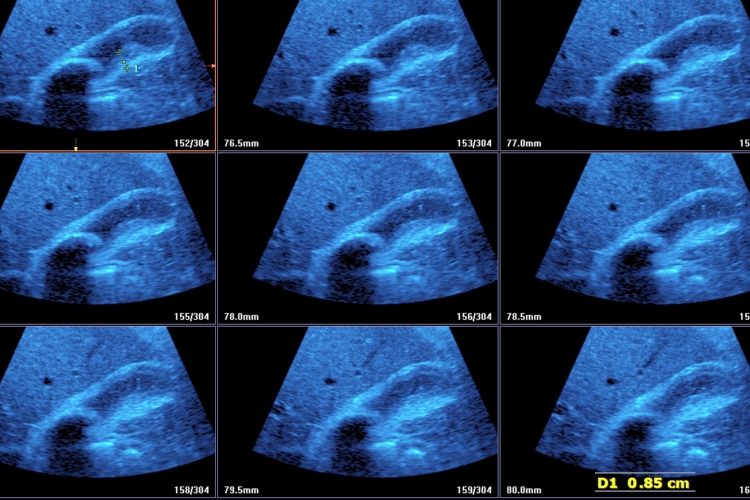

• Solitary Calculi:

• Multiple Calculi